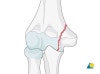

정상 골단판과의 감별이 중요합니다(정상측과의 사진 비교가 도움이 됩니다).

주관절 탈구시 관절내의 골편의 유무를 확인합니다.